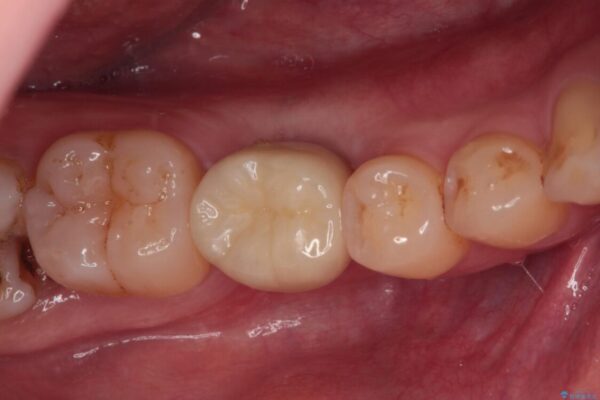

奥歯のセラミックがすぐに壊れる 欠損した奥歯へのインプラント治療

奥歯のセラミックがすぐに壊れる 欠損した奥歯へのインプラント治療 ビフォー 奥歯のセラミックがすぐに壊れる 欠損した奥歯へのインプラント治療 アフター

歯が欠損したままの奥歯のクラウンが欠けているとのことで来院された患者様です。